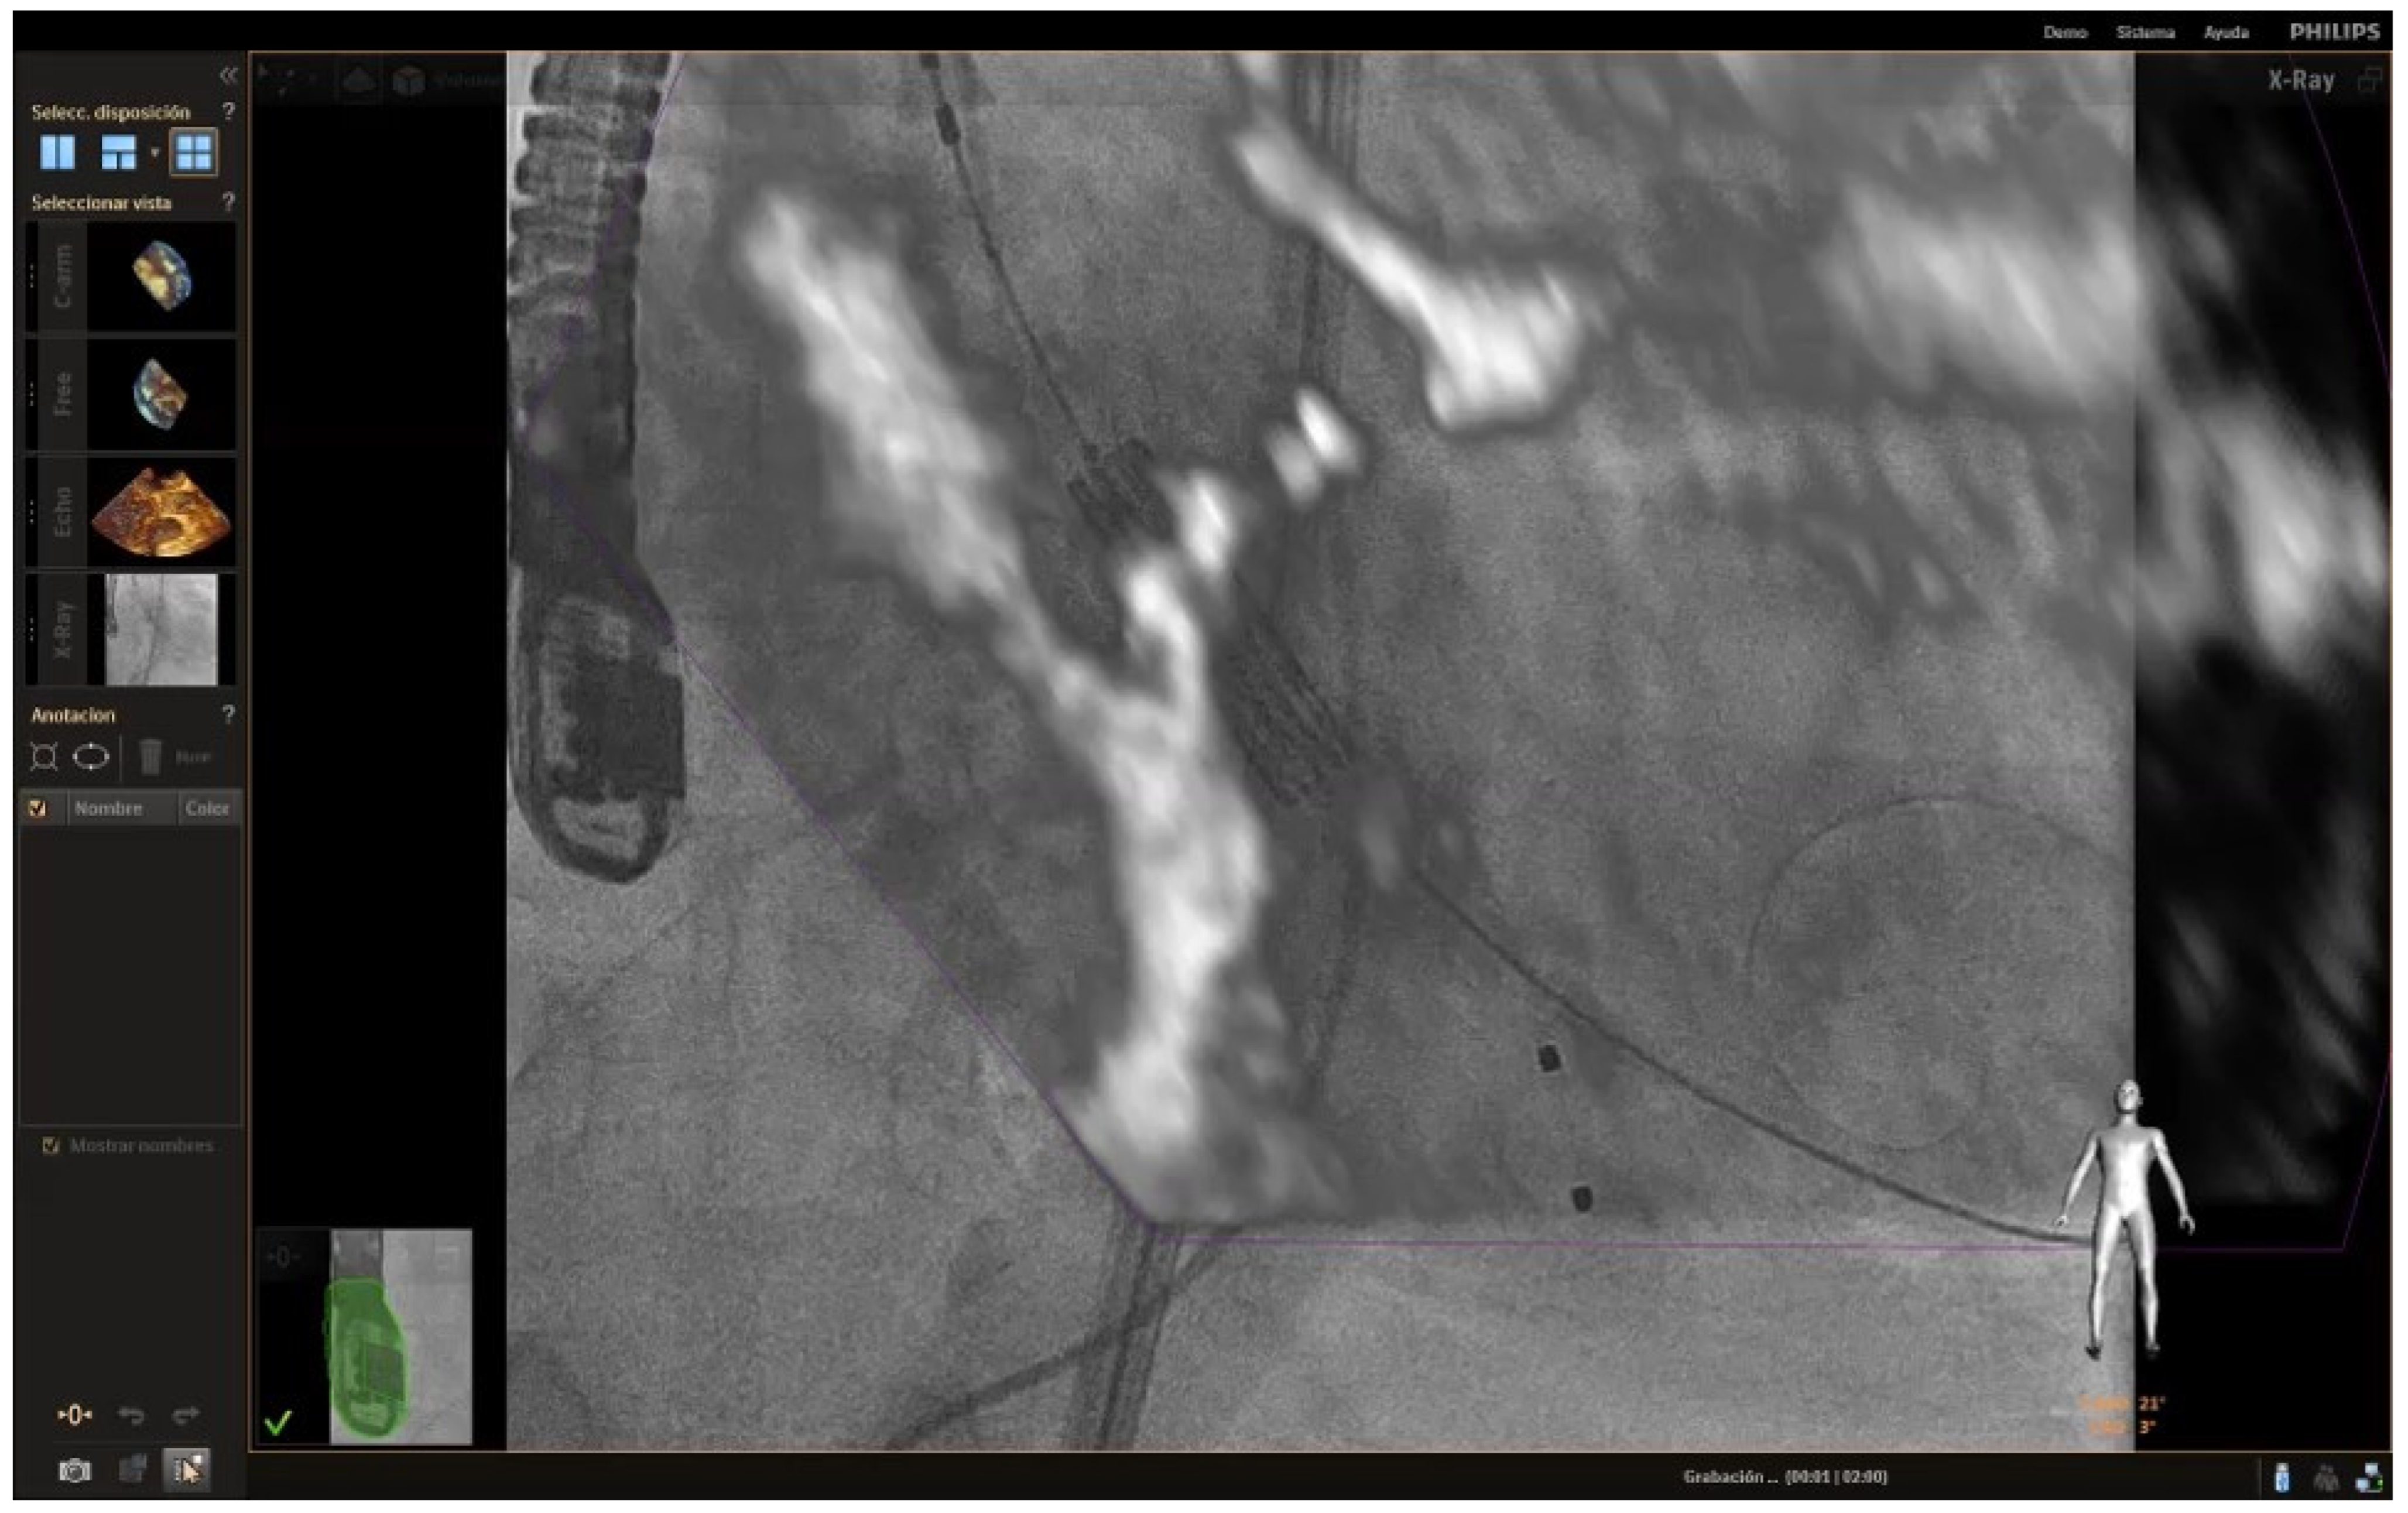

Another great advance that is coming is new fusion techniques, which make it possible the fluoroscopy and the echocardiogram image to be seen simultaneously superimposed on the screen (Figure 7). This tool allows procedures to be monitored with greater security and makes it possible to reduce the amount of contrast used. The combination of these two great advances will provide the opportunity to do the procedures much faster and more safely for the patient.

Figure 7.

Fusion imaging showing the TAVR just before its deployment at the level of the aortic annulus.